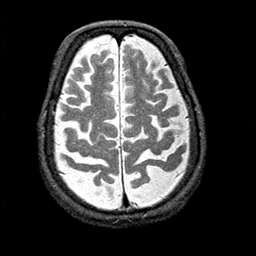

Alzheimer's disease MR T2-weighted -- Slice #37

[Home][Help][Clinical][Tour 1][Tour 2] Slice 37